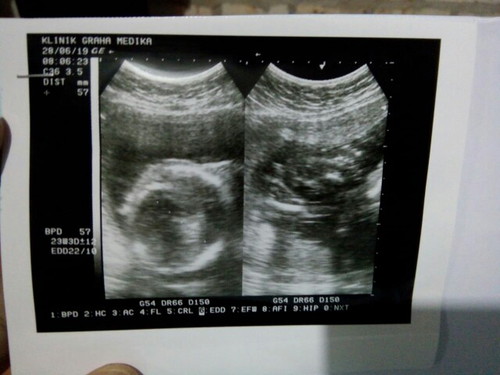

usg

Bu kmrin saya usg.. da yg tau gk ya utk detak jantung tinggi dan bb si baby trimaksih

Biasanya klo kita print usg ny ada bun brp bbj nya,klo detak jantung pas Usg didengerin sambil si dokter ngmg sekian2 bagus apa nggaknya dtk jantung baby. Tpi di print Usg bunda gak ada bbjnya

Difoto bun ga ada keterangan detak jantung+bbj nya kok

Ini klinik graha medika kurdi bukan bun?